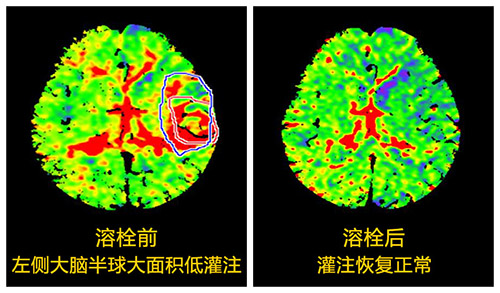

張靜波聽完電話直奔醫(yī)院,同時(shí)她用手機(jī)指揮臨床一線醫(yī)生進(jìn)行應(yīng)急處理。隨后張主任對(duì)患者進(jìn)行了多模式CT評(píng)估,判斷他的條件已符合溶栓治療,再加上自己多年的溶栓經(jīng)驗(yàn),她決定對(duì)其進(jìn)行溶栓治療。經(jīng)過一個(gè)多小時(shí)的精心溶栓,患者的上肢和下肢竟奇跡般的動(dòng)了起來,他終于脫離了生命危險(xiǎn),家屬因此非常感激。

“這是我進(jìn)行超時(shí)間窗急性腦梗死溶栓治療的患者之一,也是溶栓時(shí)間比較長(zhǎng)的一個(gè),雖然滿足溶栓的要求,可他畢竟已錯(cuò)過溶栓的黃金時(shí)間窗,心理還是有些緊張。但患者當(dāng)時(shí)情況危急,如不及時(shí)治療,他一側(cè)身體就會(huì)偏癱、麻木,還會(huì)失語(yǔ),嚴(yán)重時(shí)將會(huì)危及生命,為了挽救患者,我愿傾盡全力。”,張主任說,“之后患者把我推薦給他的朋友、鄰居、同事,并說有類似的病一定要來找我,直到現(xiàn)在還會(huì)隔三差五打電話,早就成了老朋友。”

2007年張靜波師從全國(guó)神經(jīng)科的領(lǐng)軍人物——北京天壇醫(yī)院院長(zhǎng)王擁軍教授,他是國(guó)家最早“十一五”研究項(xiàng)目的領(lǐng)頭人,她跟隨王擁軍教授學(xué)習(xí)并參與其研究項(xiàng)目。經(jīng)過自身的艱苦奮斗以及團(tuán)隊(duì)的精誠(chéng)合作,終于在2007年她在國(guó)內(nèi)率先開展了《多模式CT指導(dǎo)的擴(kuò)大時(shí)間窗急性腦梗死溶栓治療》研究,并在中華神經(jīng)科雜志率先發(fā)表,填補(bǔ)了國(guó)內(nèi)空白,該論文2013年獲中華神經(jīng)科雜志優(yōu)秀論文三等獎(jiǎng)。共發(fā)表論文20余篇,其中SCI一篇;主編著作1部,參編著作3部,大連市科技進(jìn)步二等獎(jiǎng)一項(xiàng);遼寧省科技進(jìn)步三等獎(jiǎng)一項(xiàng)。自2007年承擔(dān)國(guó)家“十一五”課題協(xié)作項(xiàng)目、國(guó)家新藥平臺(tái)、衛(wèi)生行業(yè)科研專項(xiàng)、“十二五”、“十三五”等多項(xiàng)研究課題,都取得了矚目的成就,并獲科研經(jīng)費(fèi)150余萬元。